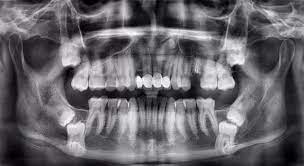

• Chụp phim CT ConeBeam 3D: Cho phép bác sĩ đánh giá chính xác hướng mọc, vị trí dây thần kinh và các cấu trúc quan trọng.

Bác sĩ Nguyễn Gia Bảo nhấn mạnh: "Không phải răng khôn nào cũng nhổ, nhưng cần theo dõi định kỳ 6 – 12 tháng/lần. Nếu có viêm, sưng, sâu răng số 7 thì cần nhổ sớm." Bác sĩ cũng khẳng định rằng nhổ răng khôn hiện nay nhẹ nhàng, an toàn, không như nhiều tin đồn thất thiệt trên mạng.

Răng khôn không phải lúc nào cũng cần nhổ, nhưng lại tiềm ẩn nhiều biến chứng nếu chủ quan. Việc nhổ hay giữ phải do bác sĩ đánh giá dựa trên hình ảnh X-quang và tình trạng cụ thể của từng người.